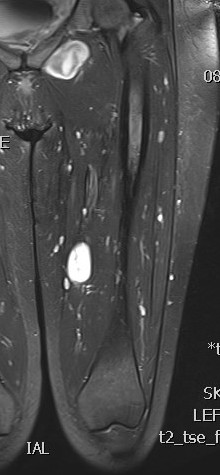

MRI

Target sign

- hypointense centrally

- hyperintense peripherally

Neurofibroma sciatic nerve